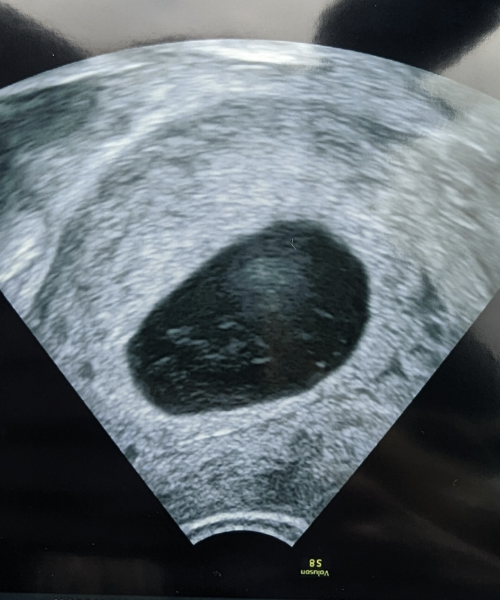

I paid to have a transvaginal the same day because of BH weekend. At this place they put it down as a "unknown location". He showed me the sac which measured around 27mm and said it's empty. He could see white bits (see pic) but that he can't say what this is. I already know it's not ectopic because I seen the heartbeat.

Can I ask, what would the white bits be? I mean my eyes play tricks and I swear I make out the shape of a foetus but thats what our minds do. Is this part of the foetus that have been reabsorbed?? :(